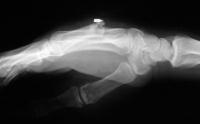

The injury: point blank handgun injury, palmar to dorsal through the middle metacarpal. Contusion of the third web space common digital nerve.

Click for larger image